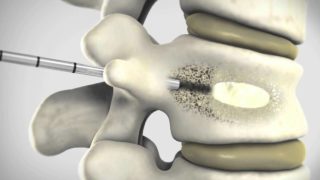

Инновационный метод лечения разработан в 1984 году во Франции. Необходимо проколоть тело позвонка тонкой иглой, залить специальный укрепляющий раствор. В результате происходит цементирование. Позволяет предотвратить появление компрессионных переломов. Применяется при отсутствии поражения нервных окончаний. В стадии агрессивного роста не применяется.

Пункционную вертебропластику проводят для прекращения роста гемангиомы и фиксации пораженного позвонка. С такими целями в полость нужного новообразования вводят костный цемент.

В тех случаях, когда гемангиома имеет большие размеры относительно позвонка или приобретает агрессивный характер (начинает расти), необходимо выполнить вертебропластику – операцию, направленную на предотвращение дальнейшего роста гемангиомы и укрепления позвонка, иначе может возникнуть неврологический дефицит, причины которого уже описаны выше.

Факторы лечебного воздействия вертебропластики:

- Анальгетический - достигается замещением гемангиомы костным цементом, что влияет на патогенетические механизмы боли, кроме того происходит разрушение части болевых рецепторов тела позвонка под действием температуры;

- Стабилизирующий - обусловлен увеличением прочности тела позвонка;

- Противоопухолевый - происходит химическое воздействие на ткань опухоли костным цементом.

Вертебропластика или точнее чрезкожная вертебропластика выполняется под местной анестезией с использованием любого местного анестетика (новокаин, лидокаин и т.д.). Благодаря местной анестезии хирург может контролировать ощущения пациента, что позволяет свести до минимума риск повреждения нервных структур во время операции. Вертебропластика обязательно выполняется с использованием постоянного рентген-контроля с помощью ЭОПа (электронно-оптического преобразователя) или С-дуги, что одно и то же. Специальная игла после обезболивания проводится через кожу, мышцы и ножку дужки позвонка в тело позвонка с той стороны, где находится гемангиома. Затем через иглу вводится в тело позвонка с гемангиомой специальный костный цемент, который быстро застывает. Гемангиома разрушается, заполняется цементом и перестает расти, а тело позвонка укрепляется.